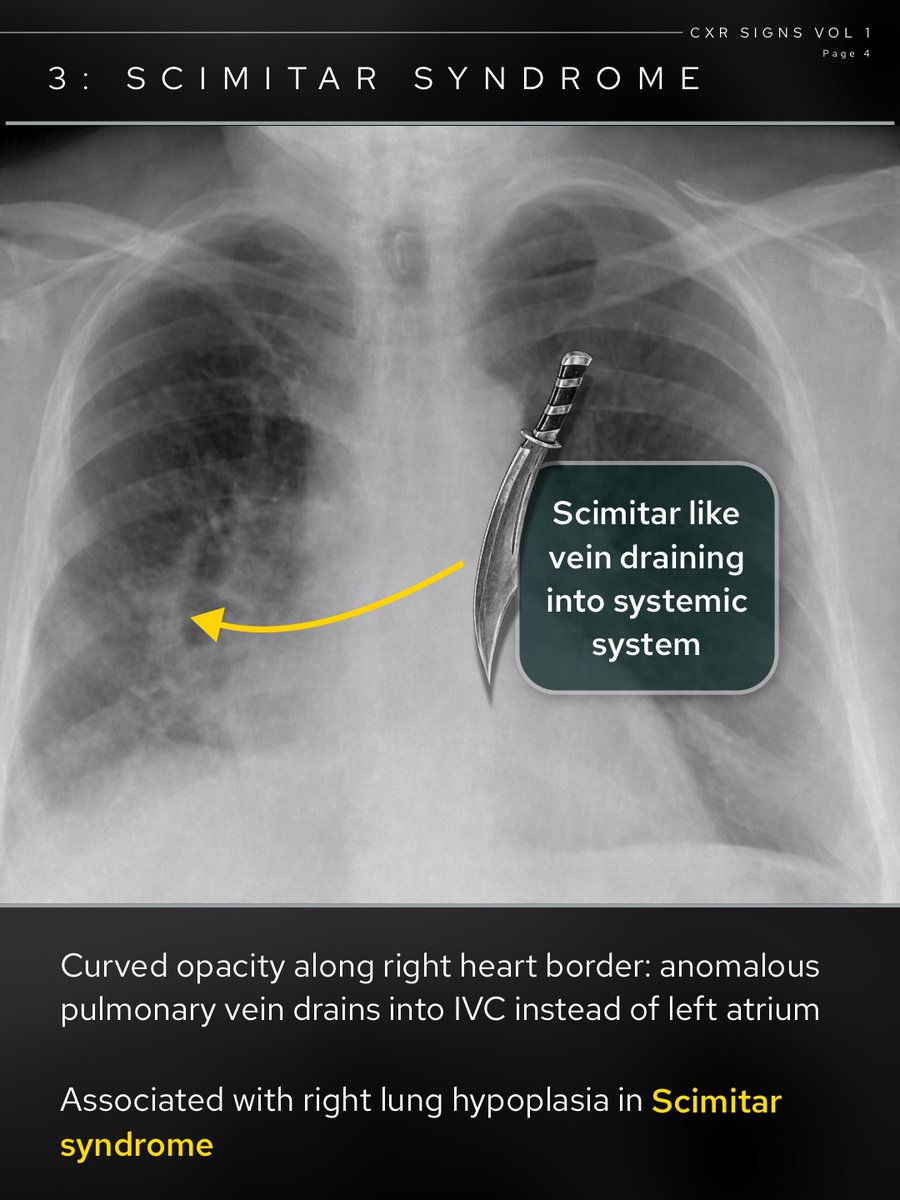

theRadiologist@radiologistpage·

How many of these chest X-Ray signs do you recognise? 🧵

theRadiologist tweet mediatheRadiologist tweet mediatheRadiologist tweet mediatheRadiologist tweet media